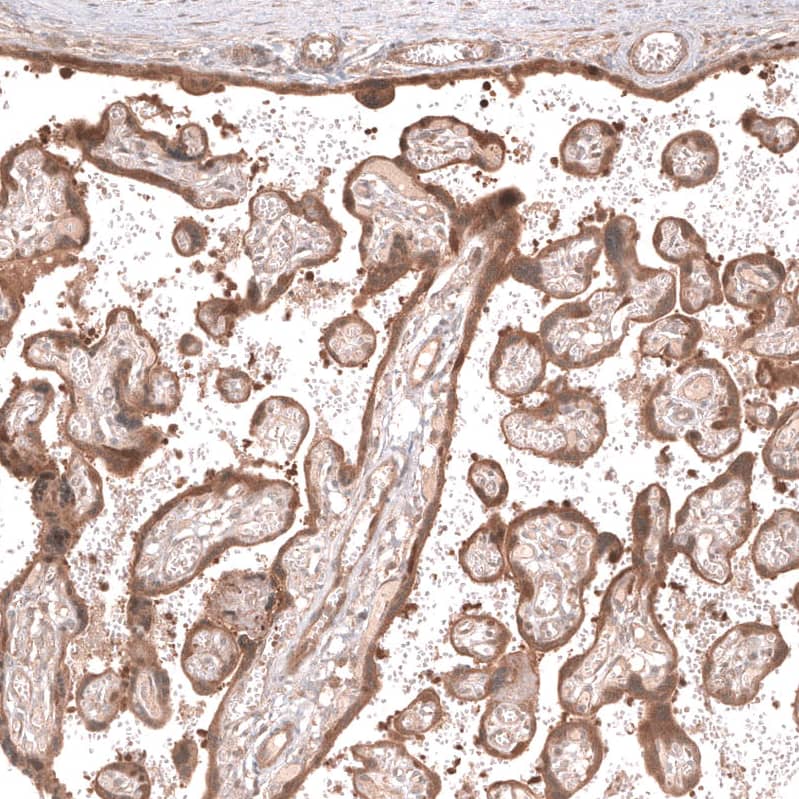

Staining of human placenta shows moderate cytoplasmic and membranous positivity in trophoblastic cells.